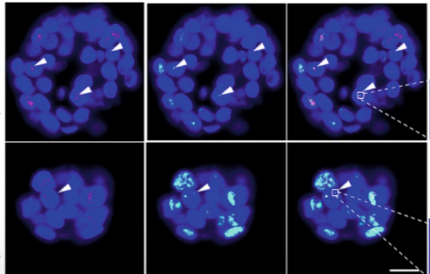

Unravelling pathways that control immortalization using tumor organoids

p-care partner Stefan Schoeftner and his team at the University of Trieste publish a scientific article involving the use of tumor-organoids to provide insights into mechanisms of cancer cell immortalization (Nature Communications)